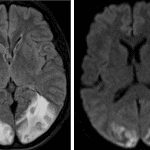

- Confluent areas of white matter hypoattenuation in the bilateral parieto-occipital regions with associated mild sulcal effacement

- Lesser degree of white matter hypoattenuation in the high left frontal white matter

- Intermixed small intraparenchymal hematomas bilaterally with additional linear hyperdensities which may represent cortical hemorrhage or small volume subarachnoid hemorrhage

- Posterior reversible encephalopathy syndrome (PRES)

White matter edema involving the bilateral parieto-occipital regions and to a lesser extent the high left frontal lobe. This appearance and distribution is most suggestive of posterior reversible encephalopathy syndrome (PRES). Associated small intraparenchymal hematomas in the parieto-occipital regions as well as possible small volume subarachnoid hemorrhage and resultant sulcal effacement. No midline shift or evidence of herniation. Brain MRI could further assess for associated ischemia.